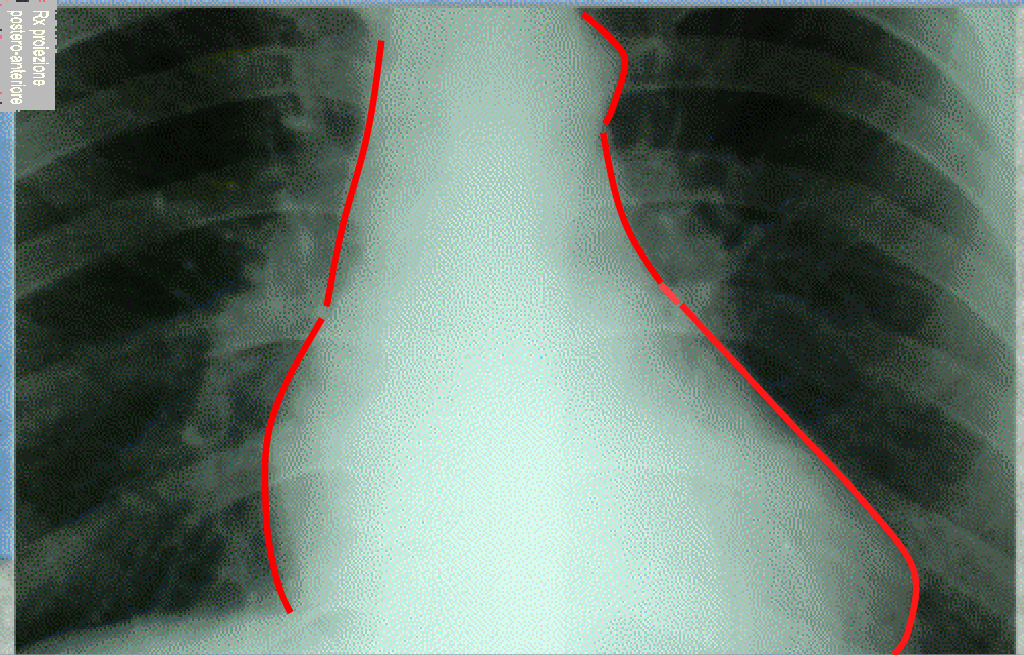

Le camere cardiache nella radiografia del torace in proiezione postero-anteriore (PA) delle camere cardiache sulla radiografia standard del Torace

In proiezione postero-anteriore (quella classica della Radiografia toracica di base) il bordo destro dell'ombra cardiaca e formato da una porzione inferiore, relativamente arrotondata, dovuta all'atrio destro (AD); da una porzione superiore, relativamente rettilinea, dovuta al margine destro della vena cava superiore (VCS) e da una piccola porzione dell’Aorta (AO) ascendente con la vena Azigos

Il BORDO SINISTRO della silouette cardiaca presenta tre archi distinti e precisamente da  due convessità  e una concavità.

Il primo arco, superiore, piccolo e convesso è formato dall’arco aortico.

Il secondo o arco medio, è rappresentato dalla concavità che corrisponde al tronco della polmonare ed alla prima porzione del suo ramo sinistro.

Il terzo o arco inferiore, il maggiore dei tre, è un'altra convessità corrisponde alla parete anteriore e laterale (o libera) del Ventricolo Sinistro (VS). Una accentuazione di questo arco esprime alterazioni del ventricolo sinistro.

All'unione del II con il III arco si trova l'auricola dell'Atrio Sinistro (AS) che normalmente appare indistinguibile.

Come si può notare che, in proiezione standard Postero-Anteriore della radiografia del torace, il Ventricolo Destro (VD) non interviene a delineare alcun profilo dell’ombra cardiaca. Pertanto le alterazioni del Ventricolo Destro si manifestano sul profilo radiografico del cuore solo in maniera indiretta sia attraverso l’arrotondamento del profilo superiore dell’arco medio di sinistra (che rappresenta l’aumento dell’arteria polmonare) sia per l’innalzamento della punta del cuore (apice cardiaco) che rappresenta indirettamente l’aumento del ventricolo destro.